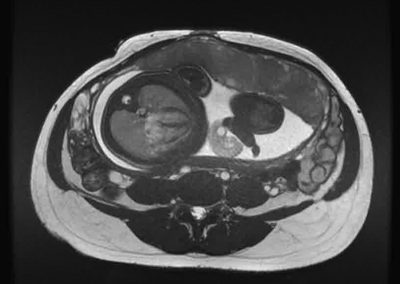

L’Université Paris Cité franchit une nouvelle étape dans le domaine de l’imagerie médicale anténatale avec l’acquisition d’un système d’Imagerie par Résonance Magnétique (IRM) 1,5T ARTIST™ de GE HealthCare. Cet équipement de pointe renforce les capacités de la Plateforme LUMIERE à l’hôpital Necker-Enfants malades, plateforme intégrée de soins, de recherche clinique et d’enseignement en imagerie médicale de la femme enceinte, du fœtus et du placenta.

L’acquisition de cette nouvelle IRM s’inscrit dans le cadre du protocole de recherche « LUMIERE SUR LE FETUS », dont les objectifs sont d’améliorer la prise en charge des pathologies anténatales, d’affiner leur pronostic et de contribuer à la réduction de la morbidité et de la mortalité à court, moyen et long terme. Cette acquisition a été rendue possible grâce au don exceptionnel de la Fondation LUMIERE d’un montant de 250k euros ainsi qu’au soutien de l’Université Paris Cité à hauteur de 670k euros.

Une plateforme au service de la recherche et des patientes enceintes

Depuis 2020, la Plateforme LUMIERE offre aux femmes enceintes volontaires, entre 16 et 36 semaines d’aménorrhée et suivies à l’hôpital Necker-Enfants malades, la possibilité de participer activement à l’avancée de la recherche en médecine fœtale, tout en bénéficiant d’une IRM fœtale au cours de leur grossesse, réalisée dans un cadre sécurisé et encadré.

L’inclusion de ces patientes, depuis leur accueil jusqu’à la réalisation des examens d’imagerie, puis l’analyse des images et l’interprétation des résultats par des équipes expertes, enrichit une base de données structurée, unique au monde, au service de la recherche et de l’innovation en imagerie anténatale et en médecine fœtale.